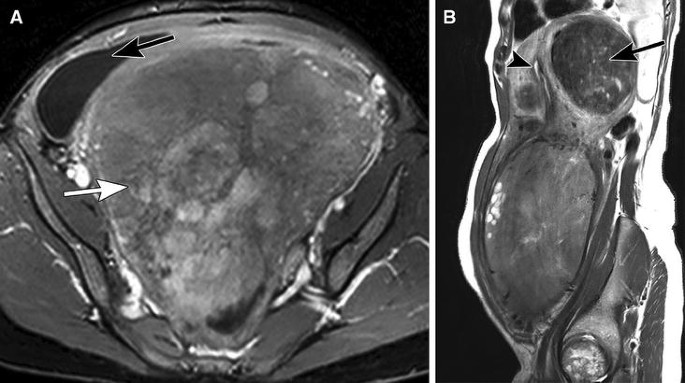

However, it is uncommon for ibs to first develop in women over the age of 50 years. Ovarian cancer is often difficult to detect in its early stages. Can ovarian cancer be found early? Current research suggests this cancer begins in the fallopian tubes and moves to the ovaries, the twin organs that produce a woman's eggs and the main source of the female hormones estrogen and progesterone. While ovarian cancer isn't common, women of any age can get it. There is no way to guarantee that you won't develop cancer in your ovaries, peritoneum (a layer of tissue that lines your abdomen), or fallopian tubes. The optimal abdominal and pelvic ct technique for staging ovarian cancer includes oral contrast media to opacify small bowel and in the absence of contraindications to intravenous contrast media, the use of intravenous contrast media is mandatory. Ovarian cancer may be an outcome of numerous environmental, physiological and psychological read this complete plan for diverticulitis diet… Any of the tissues of the ovary have the. Guide to causes, symptoms, survival rates, ovarian cancer treatment options, fertility problems, prevention guidelines. Ovaries are small organs located on each side of a women's pelvis. Because early stages of ovarian cancer are often not associated with any specific signs or symptoms, many cases are, unfortunately, diagnosed at a later and less treatable stage. Figo ovarian cancer staging effective jan.

Diverticular disease encompasses a set of colonic pathologies that result from abnormal outpouchings of the colonic mucosa (diverticula). It is serous and can be fatal. Ovarian cancer refers to several types of tumour arising from the ovaries. Like many other cancers, when ovarian cancer is found at an early stage (for example, localized to the ovary or fallopian tube) the average survival rate at five years is it is elevated by a large number of disease processes, including but not limited to, diverticulitis, pregnancy, irritable bowel syndrome. It is the leading cause of gynaecological cancer death in the uk. Because early stages of ovarian cancer are often not associated with any specific signs or symptoms, many cases are, unfortunately, diagnosed at a later and less treatable stage. Ovarian cancer is cancer in one or both ovaries. The optimal abdominal and pelvic ct technique for staging ovarian cancer includes oral contrast media to opacify small bowel and in the absence of contraindications to intravenous contrast media, the use of intravenous contrast media is mandatory. Ovaries are the female reproductive organs that produce eggs. In particular, one condition that is often mistaken for ovarian cancer is irritable bowel syndrome (ibs). There is no way to guarantee that you won't develop cancer in your ovaries, peritoneum (a layer of tissue that lines your abdomen), or fallopian tubes. Memorial sloan kettering experts discuss ovarian and breast cancer prevention and treatment in women with a brca mutation. Ovarian cancer is the medical term for abnormal and uncontrollable cell growth within the ovary that proliferates and spreads to other vital organs.